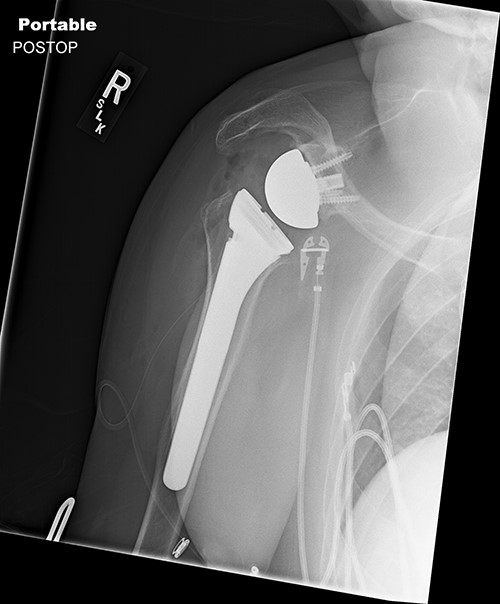

Radiologic imaging revealed bone-on-bone apposition of the glenohumeral joint, with superior humeral head migration consistent with rotator cuff tear arthropathy (Figs 1 and 2).

Grashey view demonstrating glenohumeral osteoarthritis with acromiohumeral space narrowing and superior humeral head migration.

Standard metaglene was positioned superiorly within the glenoid fossa to accommodate a 145° epiphysis and +4-mm lateralized glenosphere (Figs 4 and 5). There were no intraoperative complications.